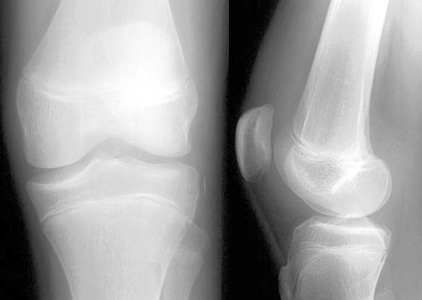

| AP and lateral knee views of a subtle fracture. | ||||||